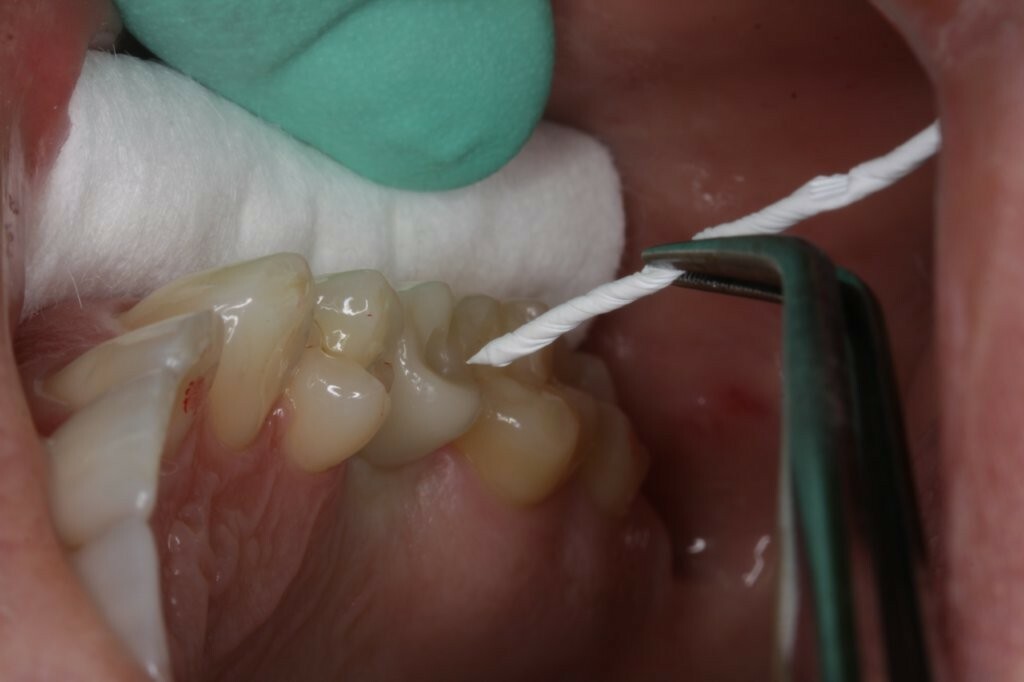

Im Mund wurde zunächst der Gingivaformer entfernt. Die Durchtrittsöffnung wurde mit Chlorhexidin (CHX) gereinigt, und das Implantat mit CHX-Gel zum Verbleib gefüllt. Danach wurde die Hybrid-Abutmentkrone behutsam in das Implantat eingesetzt. Aufgrund ihrer größeren Dimension verdrängte die Hybrid-Abutmentkrone das Zahnfleisch. Nachdem die definitive Position erreicht war und die Abutmentschraube mit einem Drehmoment von 20 Ncm angezogen wurde, wurden die Approximalkontakte mit Zahnseide und die Okklusion mit Okklusionsfolie überprüft (Abb. 28-30). Dank der hervorragenden Passung konnte der Schraubenkanal verschlossen werden. Dafür wurde die Abutmentschraube mit sterilisiertem Teflon-Band abgedeckt (Abb. 31) und dieses fest komprimiert, sodass eine verbleibende Kavität von ca. 2,5-3 mm Tiefe entstand. Dies verhindert das Eindringen von Adhäsiv und Verschluss-Composite in den Schraubenantrieb, was eine einfache und sichere Entnahme der Krone im Falle einer Revision ermöglicht.